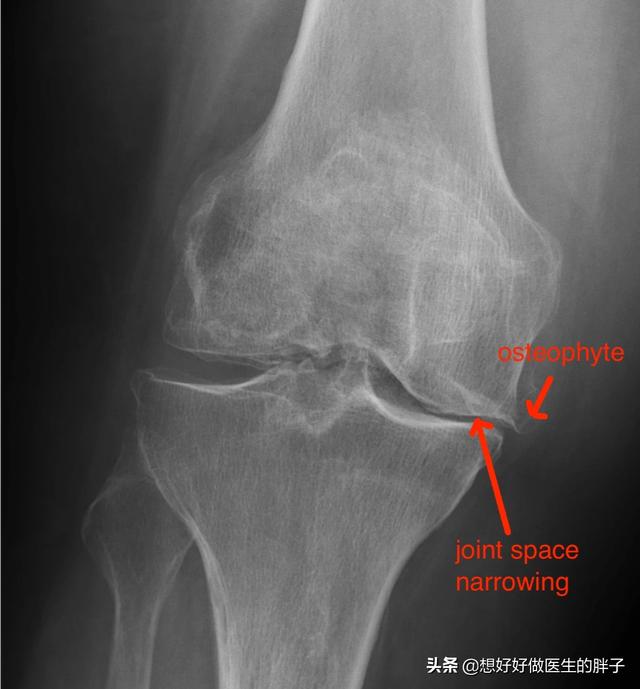

为什么有的人将骨赘称之为骨刺呢?就是因为有一些骨赘是突出骨骼范围之外的,其实这些骨赘比较小的时候,是不会对周边的软组织产生刺激和损伤的,但是如果当骨刺比较大以后,就有可能影响到周边的软组织、肌腱以及骨结构,从而产生疼痛、肿胀以及屈伸受限等症状。(下图的膝关节x线,患者就可能产生屈伸障碍、关节后方的疼痛或不适)

看到这里相信大家应该明白了,骨赘(骨刺、骨质增生)本来是帮忙的,之所以形成骨赘的基础是关节软骨的磨损,早期同时存在着纤维软骨修复、骨赘增生;晚期出现软骨的彻底破坏,表现为软骨硬化、软骨消失及软骨下局灶性骨坏死。晚期会导致严重的间隙狭窄和疼痛,需要手术解决大关节的问题。